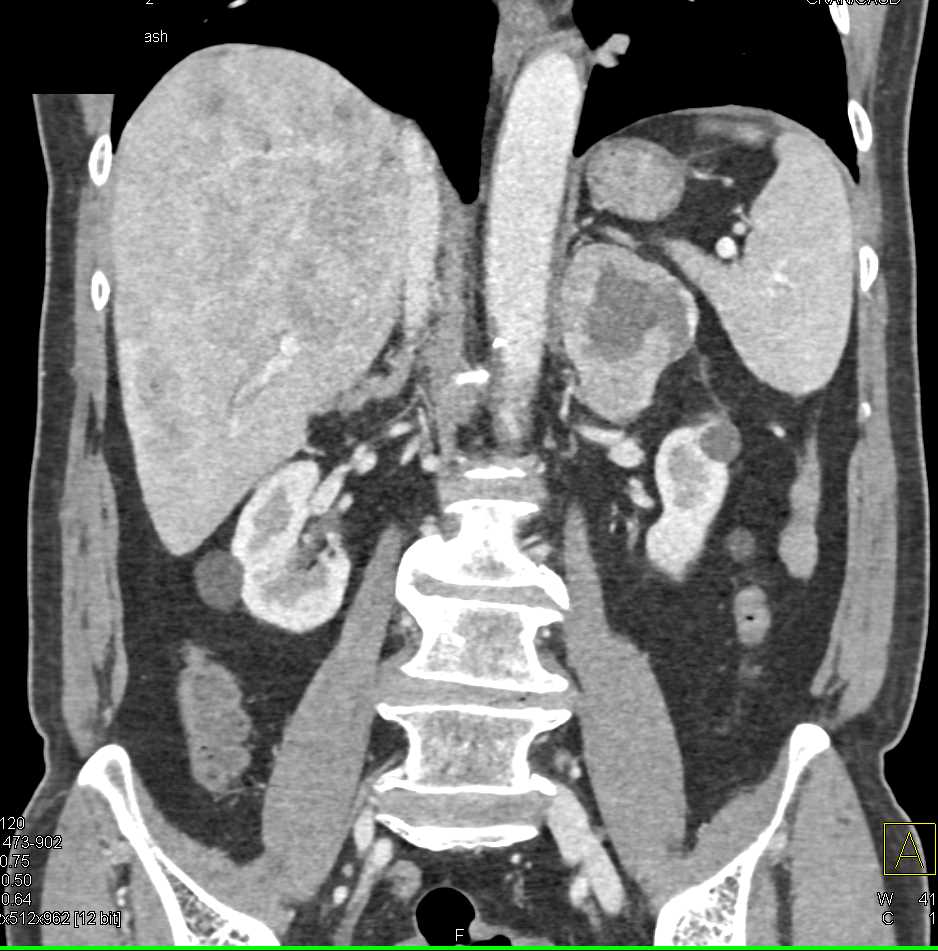

Lymphoma with Adrenal and Liver and Lung Involvement